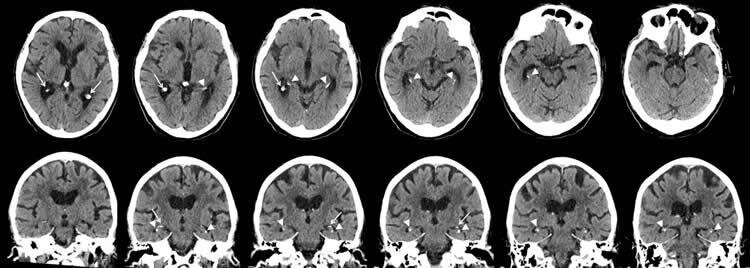

Сильная кальцификация гиппокампа (показано стрелками)

Достаточно мощное исследование охватило 1991 пациента, посетившего клинику памяти Голландского госпиталя общего назначения с 2009 по 2015 годы. Средний возраст пациентов составил 78 лет. Все участники исследования прошли когнитивные тесты и КТ-сканирование. У 19.1 процента (то есть, 380 человек) обнаружилась кальцификация гиппокампа – в той или иной степени.